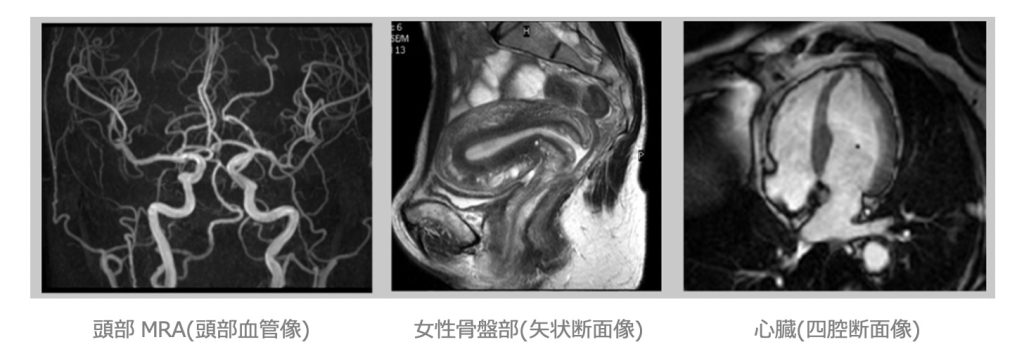

MRI 検査︓ Magnetic Resonance Imaging(磁気共鳴画像)

当院のMRI 検査は、磁気共鳴専⾨技術者の認定を受けた診療放射線技師を中⼼とし、精度管理のもと安全に⼼掛けて検査を⾏っています。

- 検査室内では装置の寝台に仰向けになり、直径約60㎝の筒の中に⼊り検査を受けます。

- 検査中は⼯事現場の様な⼤きな⾳や振動があります。

- 検査時間は、15 分〜1時間程です。

(脳:約20 分、⼼臓:約1時間、その他30 分程度)

検査中に体が動いてしまうと画像がブレてしまうため、動かないようお気を付け下さい。 - ⾳楽を聞きながら検査をお受け頂けますので、お好きな⾳楽がありましたらご持参下さい。

- 検査室では「患者様のご意向やご希望」に沿った対応を致します。不安やご質問等が御座いましたら、遠慮なく検査室スタッフにお声掛け下さい。